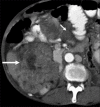

The term stromal tumor was coined in 1983 by Clark and Mazur for smooth muscle neoplasm of the gastrointestinal tract (GIT). Gastrointestinal stromal tumors (GIST) are nonepithelial tumors arising from the interstitial cells of Cajal, which express KIT protein-CD117 on immunohistochemistry. GIST can arise anywhere in the GIT, including the mesentery, omentum, and retroperitoneum.